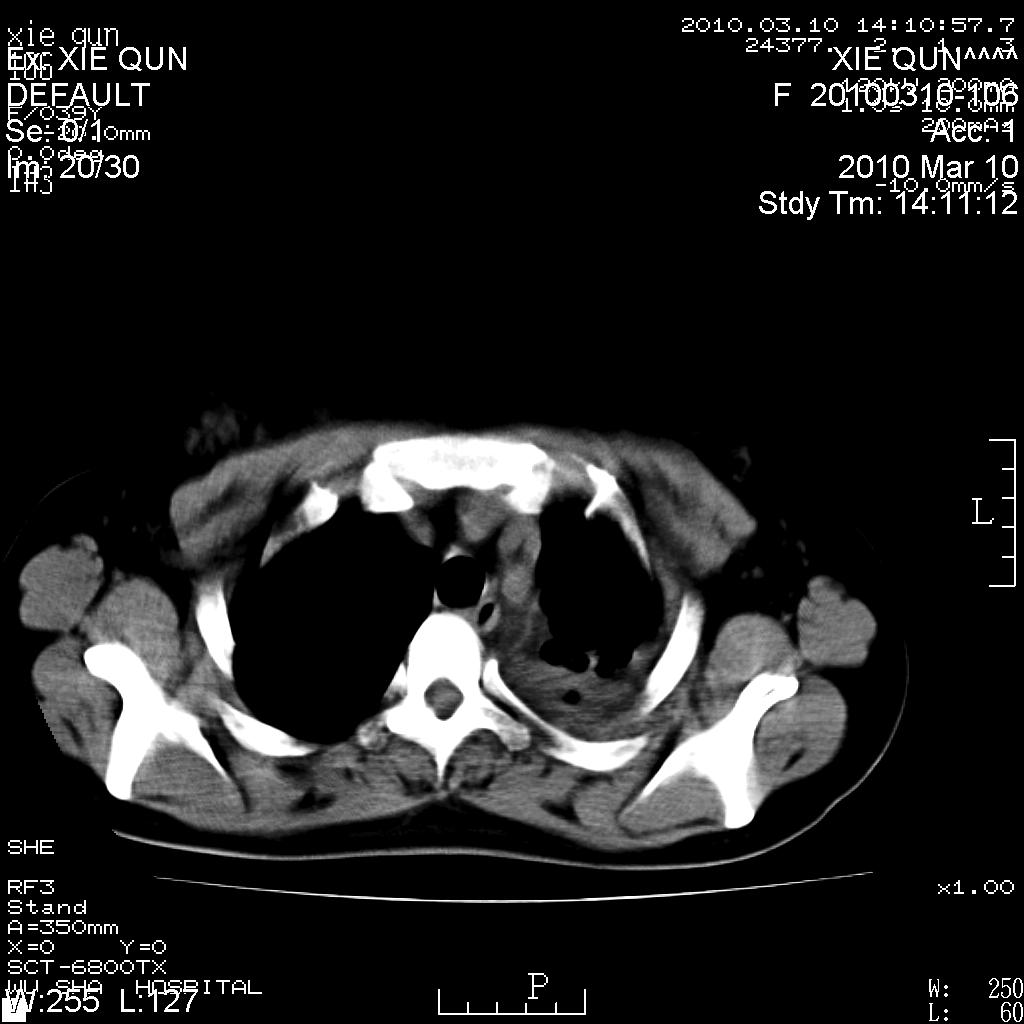

以下是引用心路寻觅在2010-3-24 17:28:00的发言:[br]两肺继发性tb左上肺空洞形成,建议痰检明确诊断。

以下是引用随光逐影在2010-3-24 19:19:00的发言:[br]两肺继发性结核并左上肺上叶空洞形成。